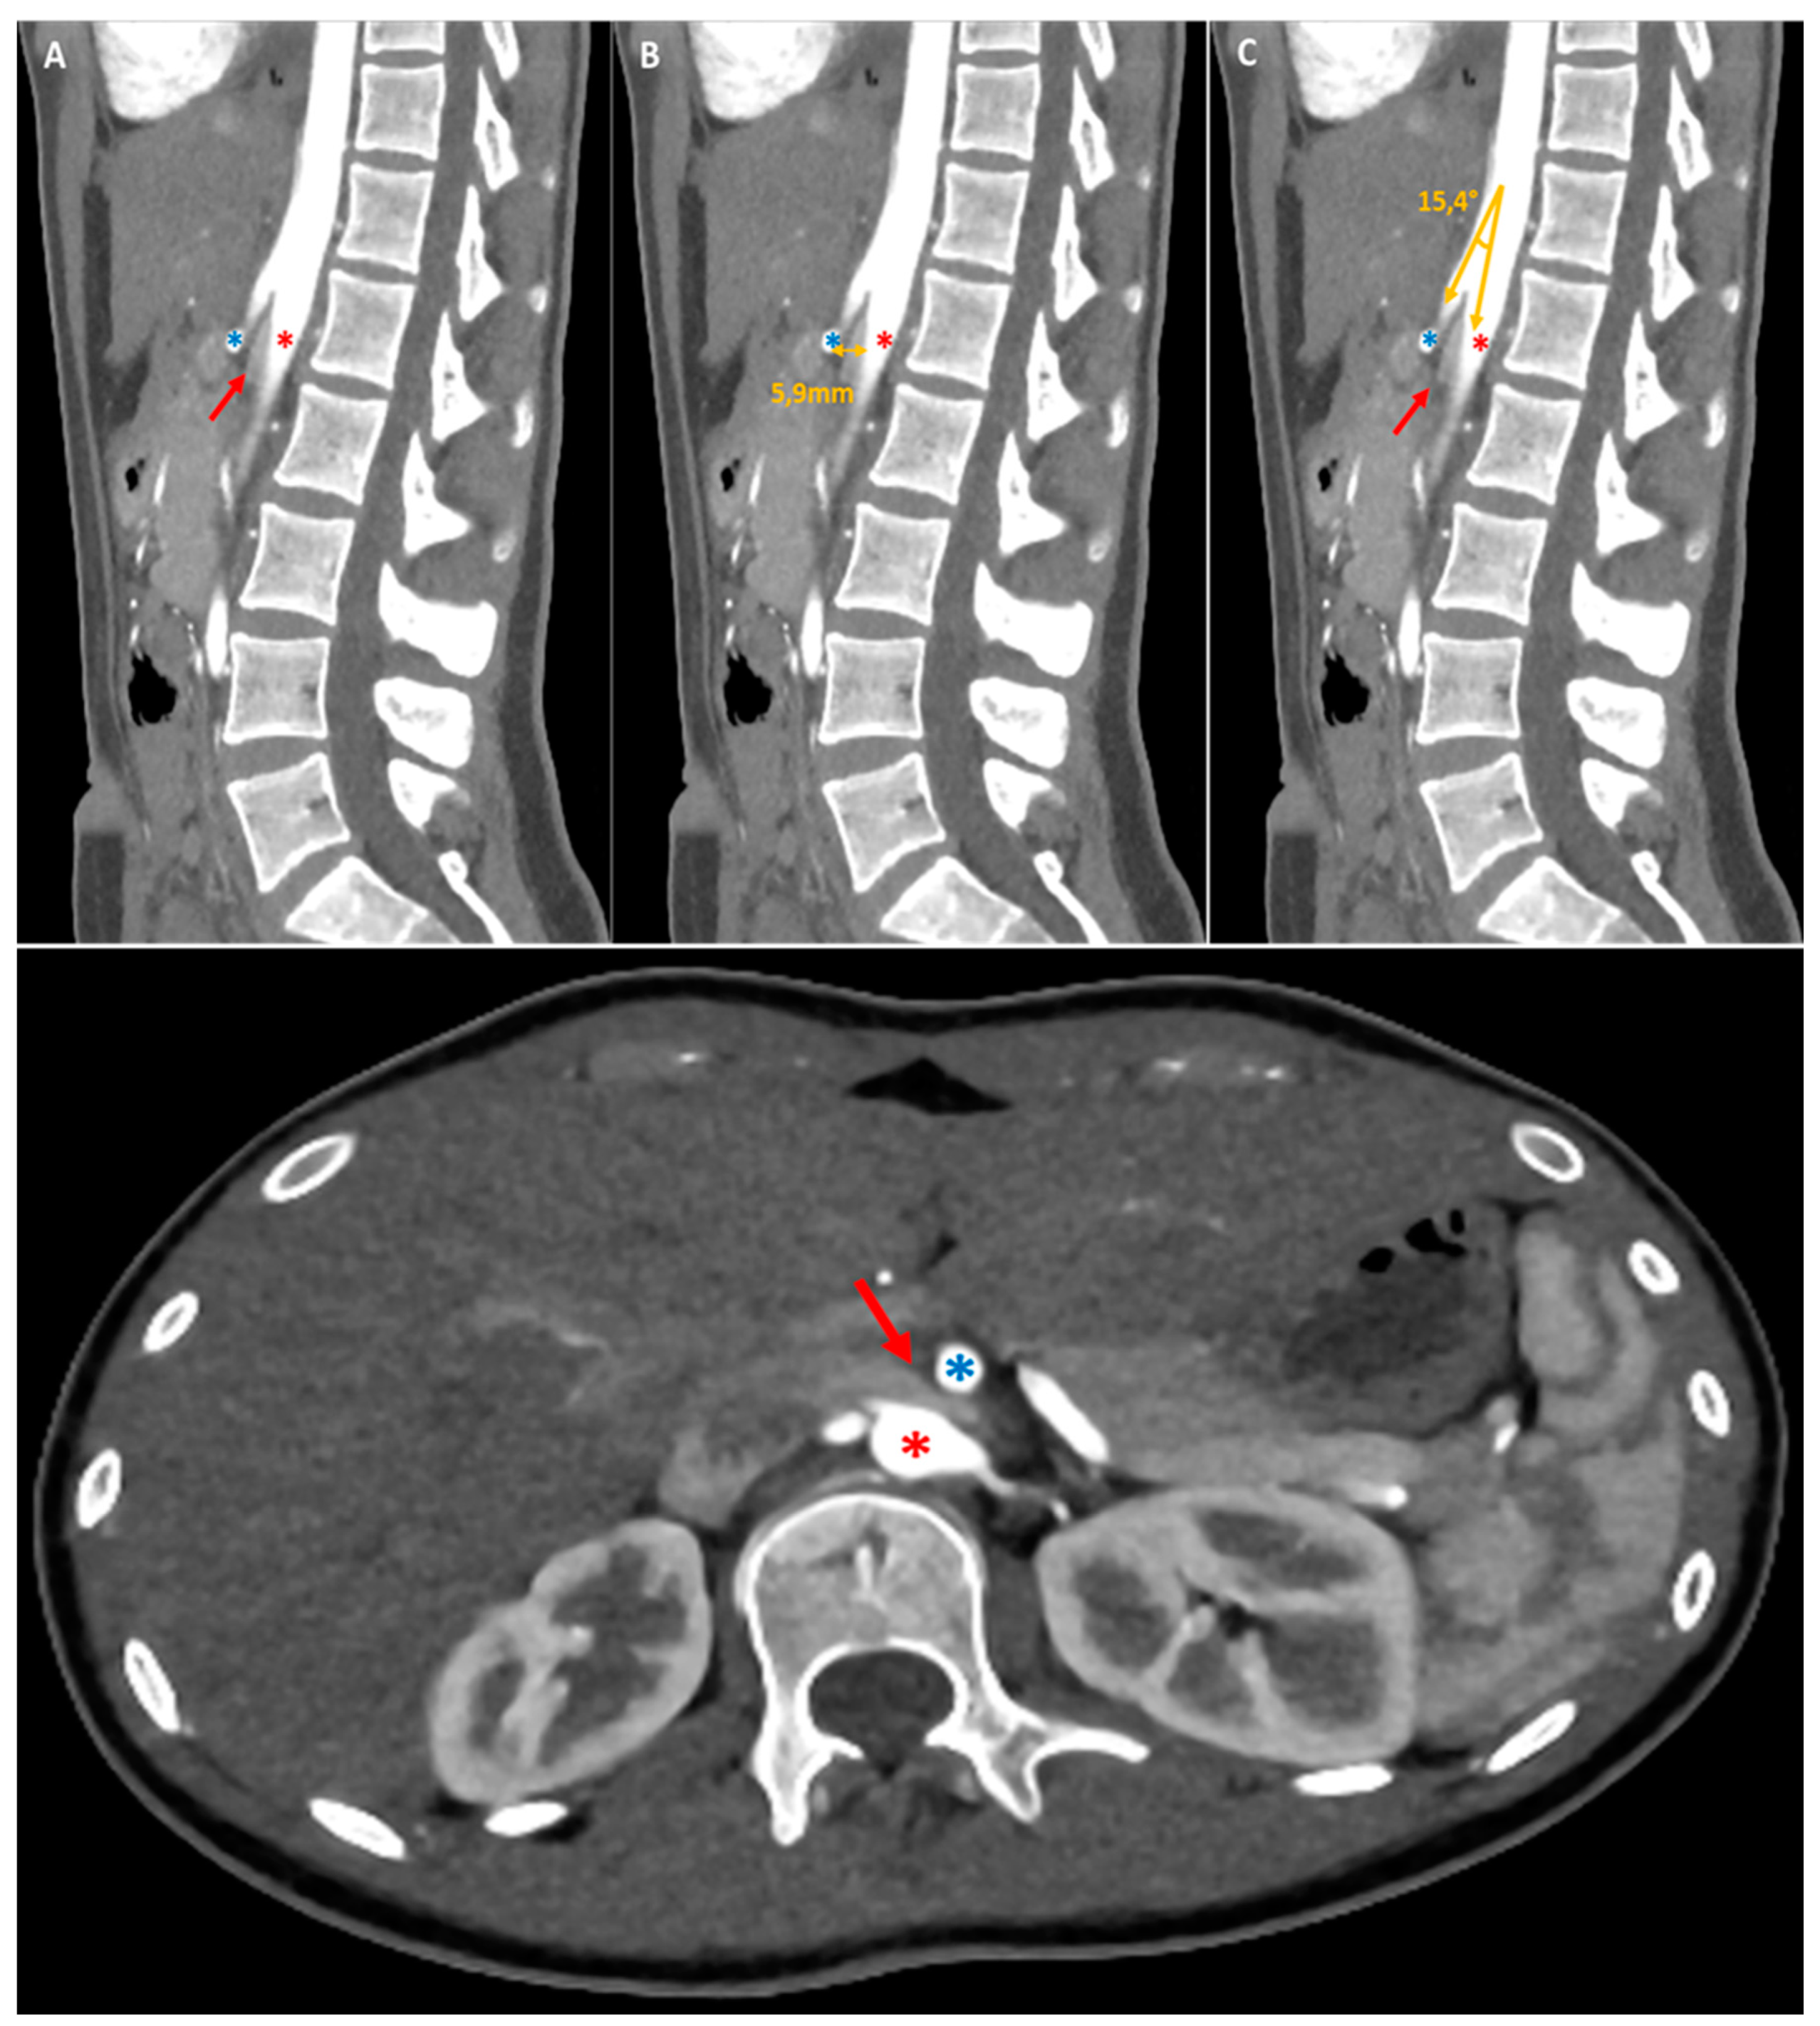

As evidenced by the existing literature, imaging has a crucial role in the diagnostic process of gastroptosis and SMAS [19]. Fluoroscopy with oral barium or iodine contrast remains the primary assessment tool of the upper gastrointestinal tract, offering real-time dynamic visualisation that facilitates the correlation of clinical history with imaging [4,19,20]. In both case, fluoroscopic findings generally include gastrointestinal distention (Figure 2, white arrows where the stomach is displaced downwards, with the greatest curvature close to the iliac crest, while the antrum remains in place), delayed gastric emptying (Figure 2, dynamic A-D) and narrowing of the third part of the duodenum (less obvious in our case). Further information can be obtained by computed tomography (CT), which, in combination with intravascular contrast, allows detailed assessment of the aorto-mesenteric vascularisation and calibre of the gastroduodenal structures, proving invaluable in the diagnosis. SMAS syndrome is characterised by gastroduodenal dilatation with marked narrowing at the junction of the AMA and the aorta (Figure 1, red arrow), shortening of the aorto-mesenteric distance (normal: 10-34mm; 1B), and tightening of the aorto-mesenteric angle (normal: 28-65°; Figure 1C) [19,20,21]. Gastroptosis may also be visible, depending on whether or not the patient has eaten prior to the examination; however, it may be less visible if the examination is performed on an empty stomach.

Figure 1. We present the case of a 17-year-old girl who presented to her general practitioner and the gastroenterology department with her parents because of epigastric pain, nausea, vomiting and significant progressive weight loss (11kg in 6 months). The patient reported a feeling of heaviness and abdominal discomfort, especially after meals, accompanied by nausea and vomiting, which had been progressive over the last few months. She explained that her appetite had remained relatively stable and that she continued to eat relatively well and healthily without changing her diet. However, she was concerned that continuing to eat would lead to a worsening of her symptoms. She had visited the emergency department several times with her symptoms and had tried various pharmacological agents, including proton pump inhibitors (PPIs) and antispasmodics, in an attempt to alleviate her condition. However, these interventions provided only minimal symptomatic improvement. The rest of her medical history was unremarkable, with no history of fever, dysphagia (solid or liquid), transit disorders, constipation or diarrhea, chest pain or dyspnea. His medical and surgical history was devoid of any noteworthy abnormalities. The family history was unremarkable. The infant was delivered via spontaneous vaginal delivery at 38 weeks of gestation with a birth weight of 2750 grams. The infant was breastfed until the age of 1.5 months, exhibited normal growth and development, and is up to date with her vaccinations. The patient's clinical parameters at the time of consultation were found to be entirely satisfactory, with the following observations: blood pressure of 120/64 mmHg, heart rate of 74 bpm, body temperature of 36.1°C, and an oxygen saturation of 100% on room air. The subject's weight was 45 kg for a height of 164 cm, resulting in a body mass index of 16.7 kg/m². On clinical examination, cardiopulmonary auscultation was within normal limits, and abdominal examination revealed epigastric tenderness radiating to the umbilicus, but no associated mass or rebound. Peristalsis of the digestive tract was noted to be intact. Given the circumstances, additional diagnostic procedures were initiated. Laboratory investigations revealed no haemogram abnormalities, no acute and/or chronic inflammation (C-reactive protein (CRP) and erythrocyte sedimentation rate (ESR) negative), preserved renal function, a satisfactory ionogram, normal thyroid function (TSH and fT4 N) and normal phospho-calcium balance (PTH and 25-OHD normal). A test for celiac disease was negative (total IgA and anti-transglutaminase antibodies normal). Faecal calprotectin (FC) levels were also normal (<100 µg/g, N <100 µg/g), ruling out inflammatory bowel disease (IBD). An endoscopic examination of the stomach revealed erythematous gastritis, with no additional microscopic abnormalities identified. An abdominal computer tomography scan (CT-scan) with injection of contrast medium demonstrated a duodenal stricture over a mesenteric pinch (Figure 1, red arrow). Furthermore, a barium radiographic examination was carried out and shown severe elongation of the stomach down to the umbilicus, suggestive of gastroptosis (Figure 2, white arrows). The patient was diagnosed with gastroptosis associated with superior mesenteric artery syndrome.